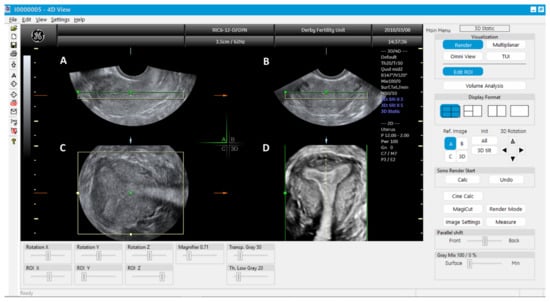

Once the 3D acquisition is completed, the uterus is displayed on the screen in three orthogonal planes (A, B, C), which can be viewed in various different modes according to the US machine used (Figure 6 and Figure 7). The default display is in the sectional mode and the operator can choose the render mode, which enhances the contrast between the two areas by recreating an impression of depth and improves visual perception. The operators should familiarise themselves with manipulation of the uterus in the three planes using the X, Y and Z functions on the US console.

When the render mode is selected, a region of interest (ROI) box will appear on the screen. The ROI box should be manipulated so that it covers the endometrial cavity in its entirety. The green line of the ROI box indicates the direction of rendering and this should ideally be placed on top. Final adjustments can be made, such as curving the ROI box, along the curvature of the endometrial cavity and applying different render options, including Omniview, Volume Contrast Imaging (VCI) and HD live, which produces a more realistic image. Once the operator is satisfied with the 3D image, this can be enlarged and can correctly classify the type of CUA. The entire volume and individual image can be saved for later analysis. [18]. The post-processing of the stored image can be performed as described above on the ultrasound machine itself (commonly done) or using ‘4D view’ software in a computer (Figure 5).

Figure 6. 3D ultrasound scan of a subseptate uterus showing simultaneous display of longitudinal plane (A), transverse plane showing two endometrial echoes (B), coronal plane (C), unique for 3D ultrasound and Rendered view of coronal plane demonstrating subseptate uterus (D).